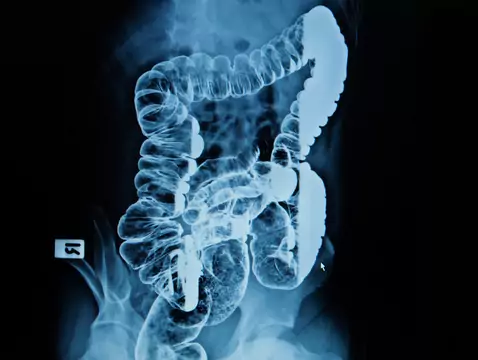

Dickdarmkrebs ist in der Regel ein Adenokarzinom. Er kommt bei Männern häufiger vor als bei Frauen. Er wird selten vor dem 40. Lebensjahr entdeckt - aber die letzten Jahre haben gezeigt, dass immer...